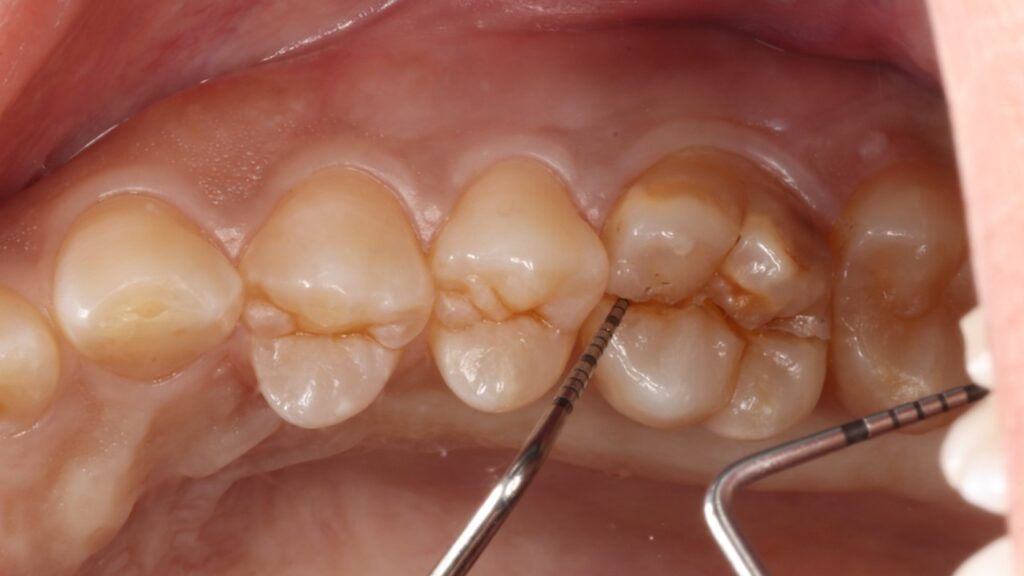

虫歯も歯周病もなく、一見何の問題もないように見えましたがマイクロスコープ(顕微鏡)で詳しく確認すると噛む力に歯が負けて真っ二つに割れてしまっていました。

このように健康な歯が真っ二つに割れることはめったにないのですが、こうなると神経に触る様な強い痛みが出ますし、CTスキャンをとると上顎洞炎にもなっていました。

歯が二つに割れてしまった場合は残念ですが抜歯するしか方法がありませんでした。